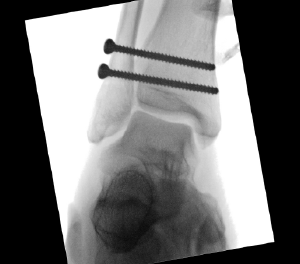

Case 2, Figure 2: 45-year-old male